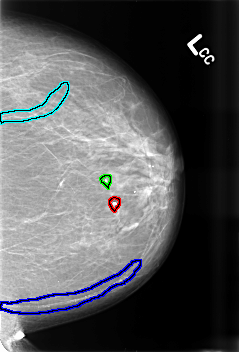

B_3429_1.LEFT_CC

FILE: B_3429_1.LEFT_CC.OVERLAY

TOTAL_ABNORMALITIES 4

ABNORMALITY 1

LESION_TYPE CALCIFICATION TYPE VASCULAR-COARSE-LUCENT_CENTERED DISTRIBUTION N/A

ASSESSMENT 2

SUBTLETY 5

PATHOLOGY BENIGN_WITHOUT_CALLBACK

ABNORMALITY 2

ABNORMALITY 3

ABNORMALITY 4